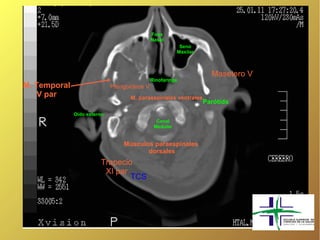

Fosa Nasal Seno Maxilar Masetero V Rinofaringe M. Temporal Pterigoideos V V par M. paraespinales ventrales Parótida Oído externo Canal Medular Músculos paraespinales dorsales Trapecio XI par TCS